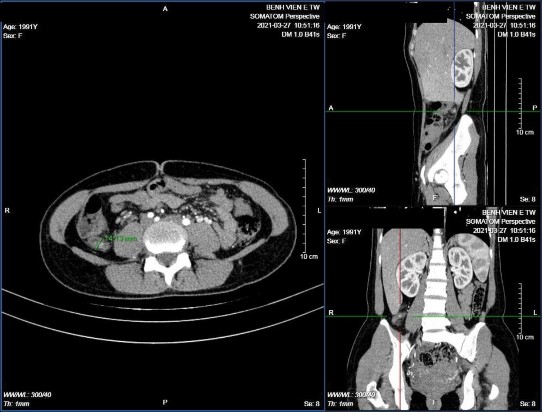

Hình 3.3: Ruột thừa ở vị trí sau manh tràng, trong lòng có sỏi phân

Bệnh nhân Hoàng Công M. 27 tuổi, mã bệnh án 2120143. GPB VRTC.

Hình 3.4: Ruột thừa nằm ở vị trí tiểu khung, trong lòng có sỏi phân.

BN Chu Tuệ M. 10 tuổi, mã bệnh án 2104324. Phẫu thuật thấy ruột thừa chạy chếch xuống tiểu khung, kết quả giải phẫu bệnh ruột thừa viêm mủ.